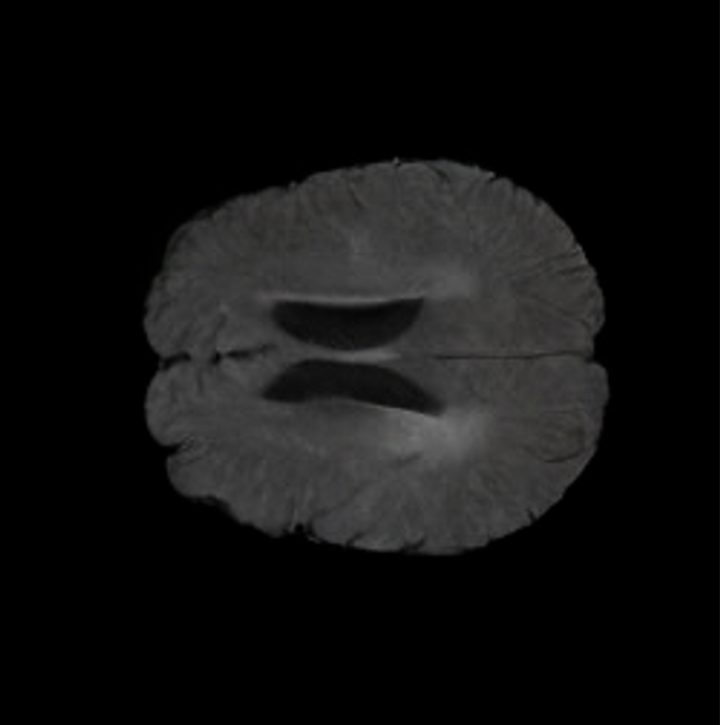

In this work, we present X-Diffusion, a cross-sectional diffusion model tailored for Magnetic Resonance Imaging (MRI) data. X-Diffusion is capable of generating the entire MRI volume from just a single MRI slice or optionally from few multiple slices, setting new benchmarks in the precision of synthesized MRIs from extremely sparse observations. The uniqueness lies in the novel view-conditional training and inference of X-Diffusion on MRI volumes, allowing for generalized MRI learning. Our evaluations span both brain tumour MRIs from the BRATS dataset and full-body MRIs from the UK Biobank dataset. Utilizing the paired pre-registered Dual-energy X-ray Absorptiometry (DXA) and MRI modalities in the UK Biobank dataset, X-Diffusion is able to generate detailed 3D MRI volume from a single full-body DXA. Remarkably, the resultant MRIs not only stand out in precision on unseen examples (surpassing state-of-the-art results by large margins) but also flawlessly retain essential features of the original MRI, including tumour profiles, spine curvature, brain volume, and beyond. Furthermore, the trained X-Diffusion model on the MRI datasets attains a generalization capacity out-of-domain (e.g. generating knee MRIs even though it is trained on brains). The code is available on the project website https://emmanuelleb985.github.io/XDiffusion/.

Notably, X-Diffusion achieves state-of-the-art dB for a few input slices while baselines require more than 60 input slices to achieve similar performance (Figure 7). The margin is more than 12 dB PSNR for the 1-slice input in both the BRATS and the UK Biobank benchmarks (see Table 1 and Figure 6). For reference, two randomly sampled MRIs from UK Biobank would have a PSNR of 15.95 dB 0.36 (on 4800 randomly sampled examples). Omitting the preprocessing step of alignment DXA to MRI, leads to a drop of PSNR on average by 2.87 dB (29.01 dB 26.14 dB). The slices from 3D reconstructed volumes at varying depths and axis of rotation, visually match the ground truths for both brain and whole-body scans (see Figures 4 and 5 left). We also plot the error map (Figure 3) and the spread of the error (Figure 5 right) of such X-Diffusion generations to highlight the differences with the ground truth MRIs.

Brain Volumes Preservation. The generated MRIs by our X-Diffusion retain almost the exact same average brain volume vs. of the real MRIs.

Tumour Information Preservation. For the brain tumor segmentation, we use a Swin UNETR model[28, 70], trained with random rotation, and intensity as data augmentation. On the test set with human ground-truth annotations (), the brain volumes generated from single slice input preserve the volume of the different tumour components (paired t-test, for all 3 classes). In Figure 4, we highlight the tumor profiles of the generated MRIs compared to the ground truth tumour profile. The real MRI Dice score in the test set is 85.15 while the generated MRIs from a single slice have a dice score of 83.09. This shows how the generated MRIs indeed preserve the tumor information and can act as an affordable and informative pseudo-MRI, before conducting an actual costly MRI examination in hospitals. More detailed results are provided in supplementary material.